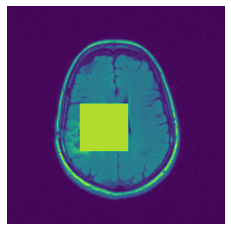

In figure 3, we present qualitative examples of different masking strategies. It is observed that, unlike context prediction and restoration, our method tends to propose targeted masks like the tumor regions or regions with abnormalities and avoids masking less helpful regions. However, it should be noted that Intelligent-Masking does not necessarily mask the tumor regions but considers all areas of interest that results in better feature learning. Examples of other masking samples are provided in supplementary materials. Furthermore, in medical images, unlike natural scenes, the structures are very local with imbalanced information throughout an image. Therefore, random masking strategies as shown in Fig 3 operate ineffectively by masking non-informative regions.

Figure 2: Qualitative examples of compared method’s strategies for masking

Figure 3: More qualitative examples of different distorting strategies including our method. We show the different self-supervised mechanisms on both datasets of MR (rows: 1-3) and ultrasound (rows: 4-6) images for lower-grade glioma and breast cancer diagnosis respectively. We include both images of normal (rows: 1,4) and cancer (rows: 2,3,5,6) conditions for each dataset. We also observe that our method treats each image based on its context information with no predetermined strategy.